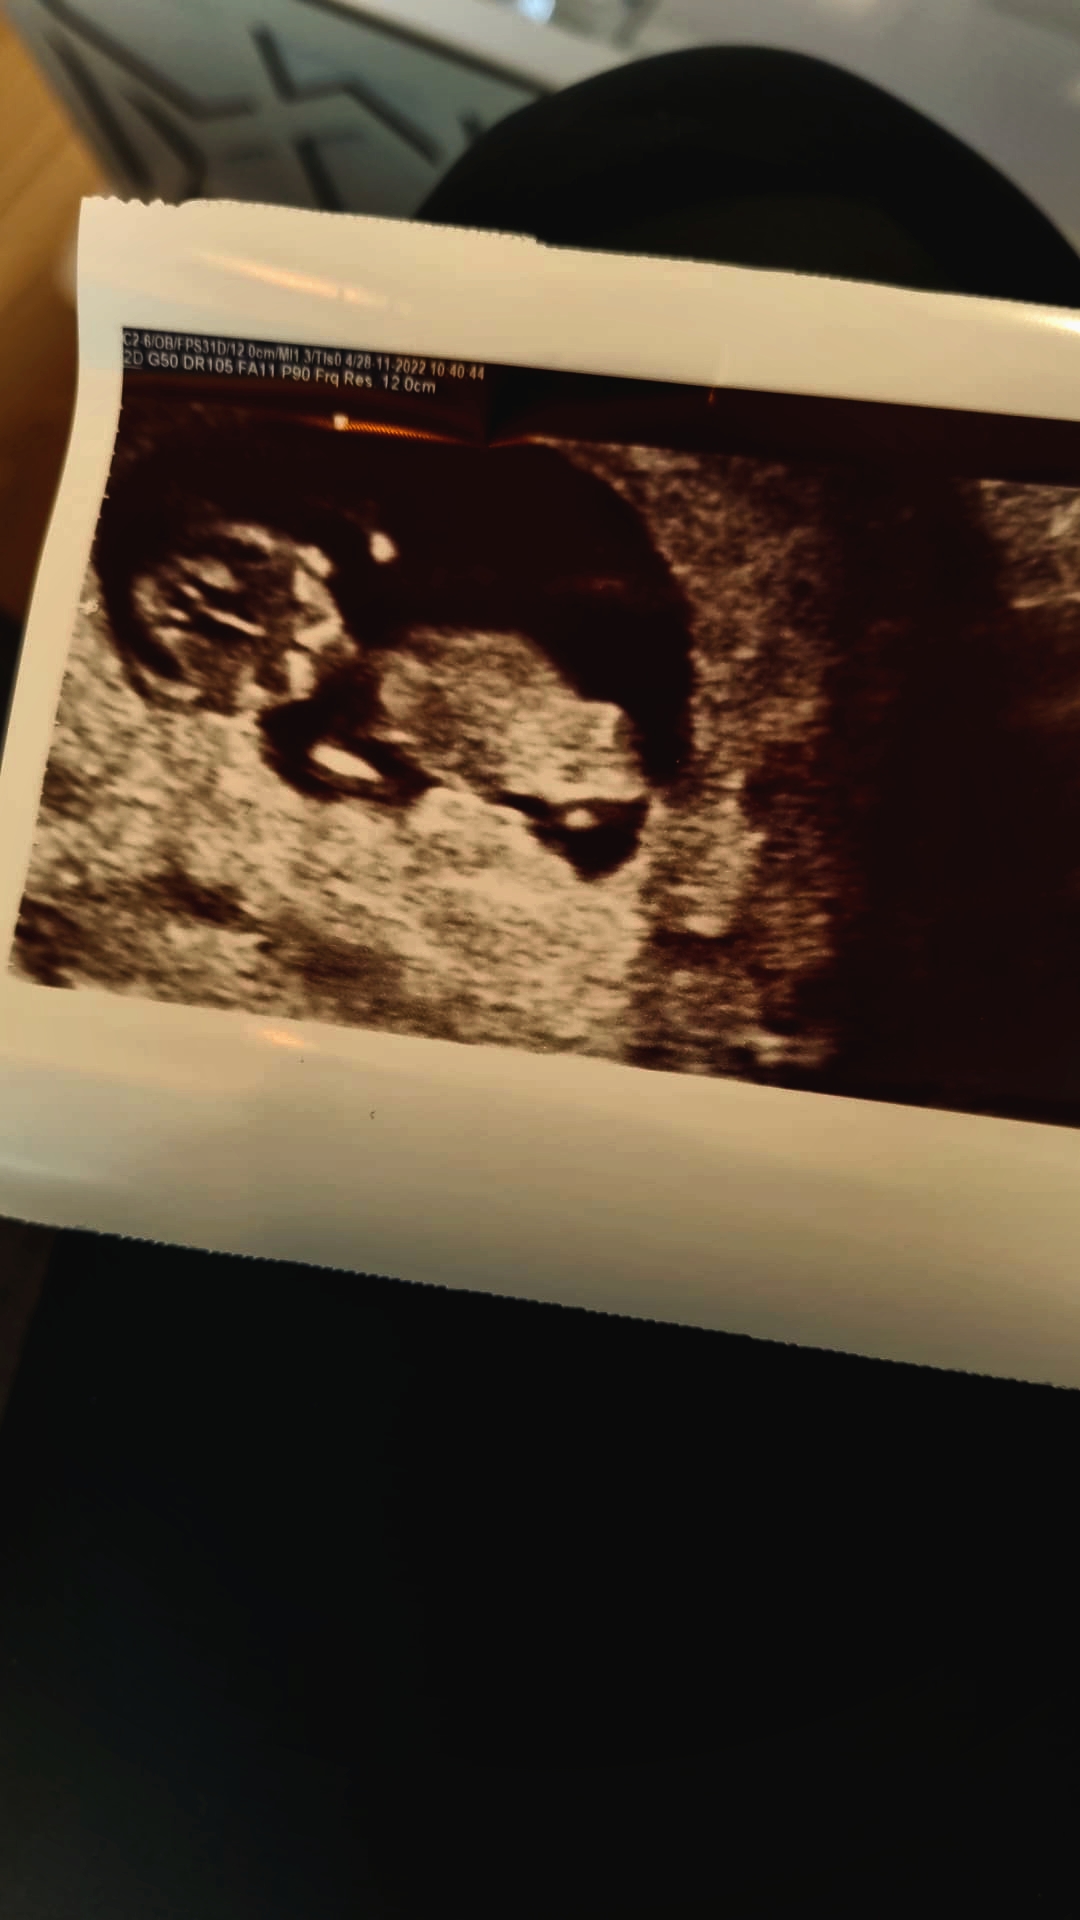

Merhabalar tekrardan 11 haftalk olmuşuz yorum yaparmısınız çok teşekkür ederim

192,5 KB · Görüntüleme: 146